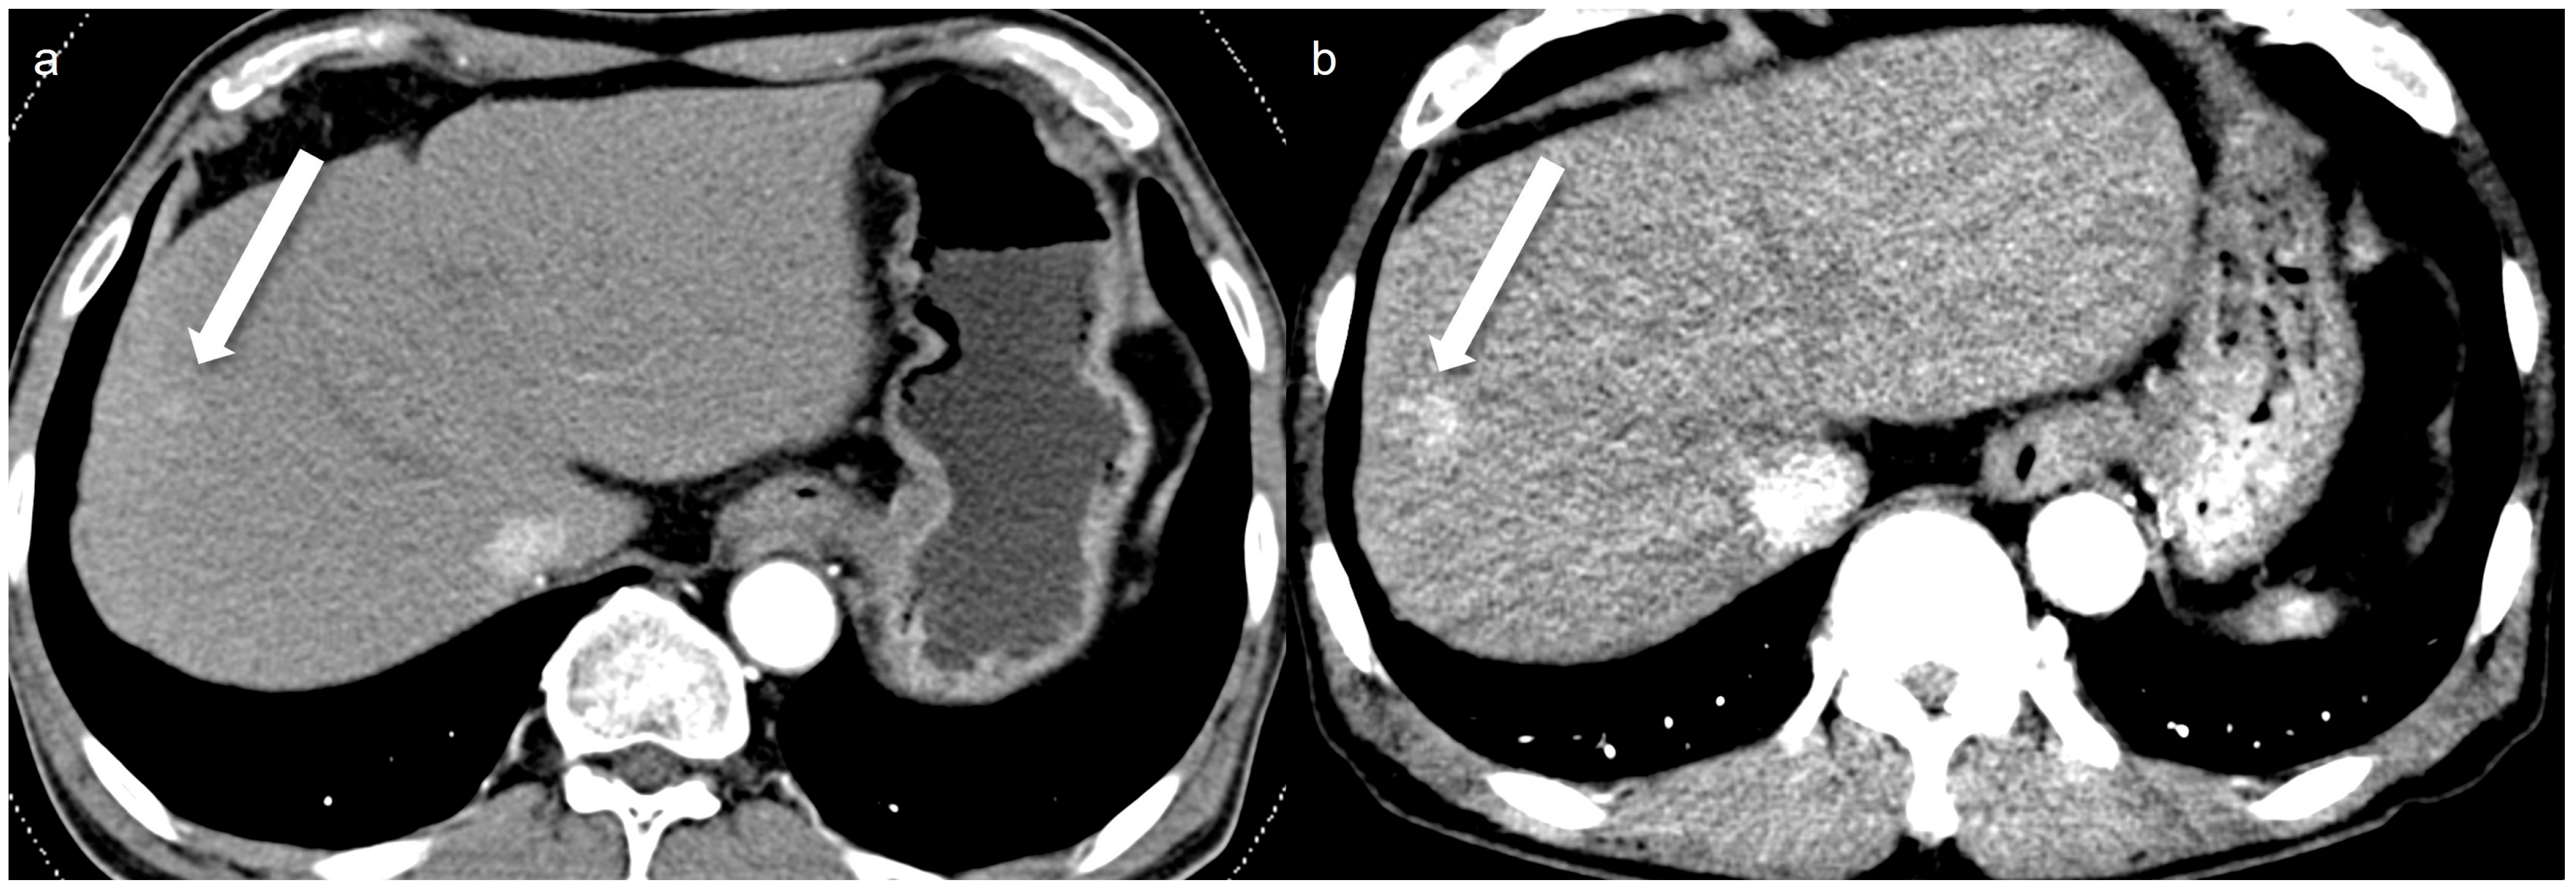

Figure 3.

A 67-year-old man with an 8 mm nodular AP shunt. A prior standard-dose CT performed 4 months ago (a) shows subtle arterial enhancing nodular lesion (arrow), whereas a low-concentration contrast medium (270 mg I/mL) monoenergetic 40 keV image (b) shows more prominent arterial enhancement (arrow). The enhanced conspicuity on the monoenergetic image highlights the potential diagnostic benefit of monoenergetic 40 keV imaging in detecting subtle arterioportal shunts.